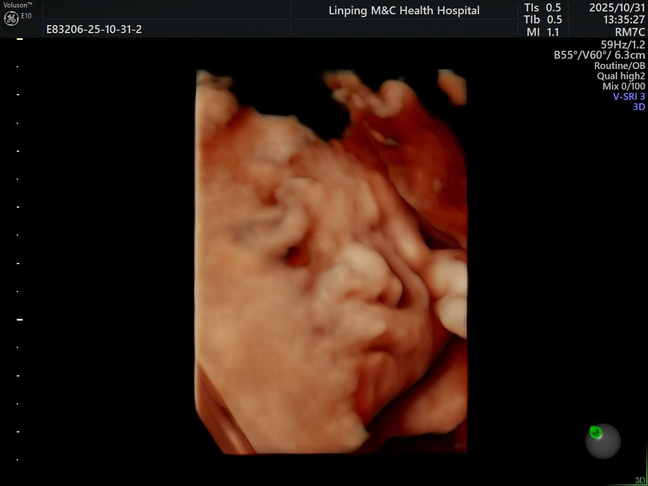

10.31 宝宝的四维照片

宝宝的四维照片